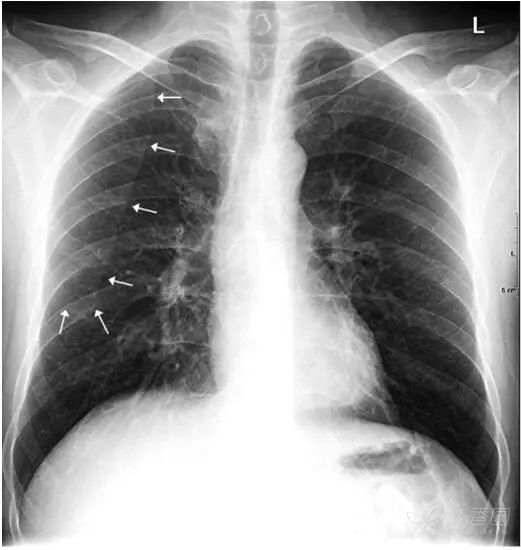

肩胛骨 如果投照时体位标准,上肢内旋充分,则肩胛骨应当位于肺野之外。否则肩胛骨将重叠于上肺野偏外的区域,呈与胸壁平行的条带状高密度影。此时可能会被误认为是肺内病变。仔细观察可见肩胛骨影从肺内向肺外延伸,即可与肺内病变区别。

上图摄片时双上肢未充分内旋,导致双侧肩胛骨大部分重叠于双肺中上肺野中外带,导致相应肺野条带状密度增高。白色箭头标示右侧肩胛骨内侧缘,向肺外延续。左侧肩胛骨情况类似。